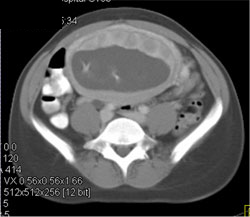

Pelvic Congestion Syndrome